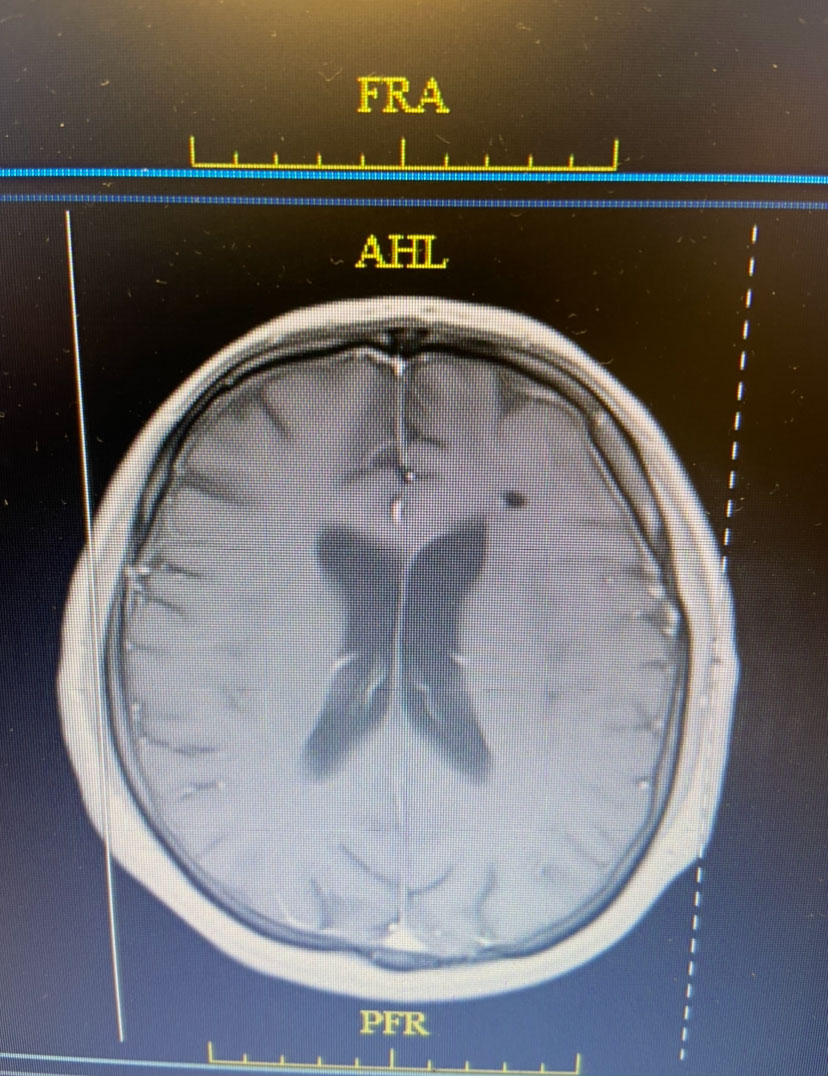

Image 1: Pre-treatment axial post contrast MRI.

This is a 50 year old man who last year had undergone gastrectomy for gastric cancer. He presented now with new onset of lethargy and aphasia, with both a receptive and expressive component . He was also experiencing intermittent bradycardia. Brain imaging showed a 3 cm ring enhancing , fluid filled mass in the left frontal region with significant surrounding edema, mass effect, and midline shift. (Image 1 shows axial post contrast MRI. ) Recent imaging of the body had shown no evidence of active metastatic disease.